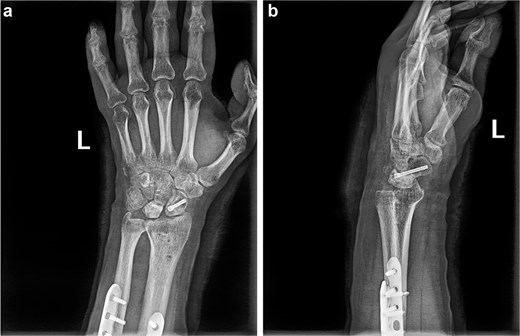

(a and b) Anterior and lateral views of the wrist joint following the second postoperative intervention, demonstrated satisfactory reduction of the fracture ends of the wrist bones, and the lunate bone had been relocated.